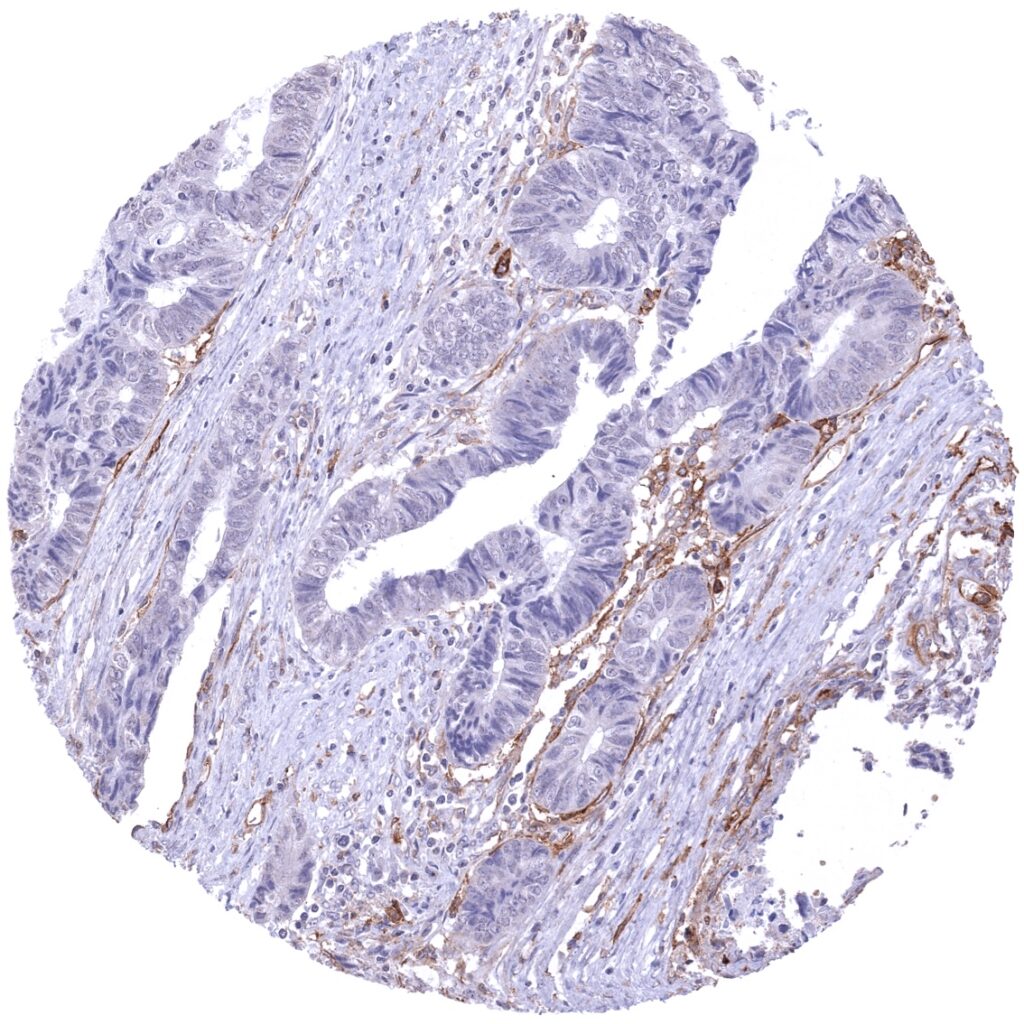

Colon - Thrombomodulin negative colorectal adenocarcinoma (Thrombomodulin immunohistochemistry).